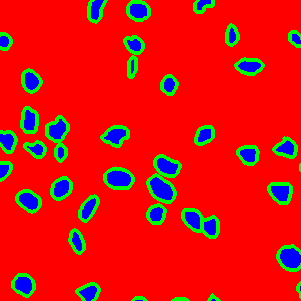

The task of nuclei segmentation can be roughly divided into two stages: the first stage is extracting the foreground(nuclei), the second stage is segmenting the connected foreground area into separated nuclei and finding out the boundary of each nucleus. Our method intends to merge these two steps by extracting the nuclei and their edges at the same time. That is the reason why it is named ”nuclei-boundary(NB) model”. As shown in Fig.3, the output of the NB model has three channels, each has the same height and width with the input image. Its values represent the probabilities of each pixel being background𝑏𝑎𝑐𝑘𝑔𝑟𝑜𝑢𝑛𝑑background, boundary𝑏𝑜𝑢𝑛𝑑𝑎𝑟𝑦boundary or inside𝑖𝑛𝑠𝑖𝑑𝑒inside class, respectively. The manual annotation for our segmentation problem is the boundary of each nucleus. A pixel belonging to the boundary𝑏𝑜𝑢𝑛𝑑𝑎𝑟𝑦boundary class means that it is on or inside an annotated boundary and within 2 pixel from the boundary. Pixels of the inside𝑖𝑛𝑠𝑖𝑑𝑒inside class are those that are inside annotated boundary but are not boundary𝑏𝑜𝑢𝑛𝑑𝑎𝑟𝑦boundary pixels. Correspondingly, the output can be regarded as an RGB image and the estimated maps of the background𝑏𝑎𝑐𝑘𝑔𝑟𝑜𝑢𝑛𝑑background, boundaries𝑏𝑜𝑢𝑛𝑑𝑎𝑟𝑖𝑒𝑠boundaries and nuclei𝑛𝑢𝑐𝑙𝑒𝑖nuclei are represented by red, green and blue, respectively, as shown in Fig.3. To generate the ternary mask for training, we apply a morphology operator to each nucleus to obtain the inside𝑖𝑛𝑠𝑖𝑑𝑒inside pixels, and then subtract inside𝑖𝑛𝑠𝑖𝑑𝑒inside pixels from the nucleus to get boundary𝑏𝑜𝑢𝑛𝑑𝑎𝑟𝑦boundary pixels.

Figure 6 shows how our method segments the nuclei step by step. The color variety is well controlled by the color normalization procedure. The prediction result shows clear nuclear areas and nucleus boundaries. In the final segmentation result and ground truth image, each nucleus is represented by a different color.

Figure 6: (a) examples of original histopathology images; (b) corresponding images after color normalization. (c) raw segmentation results by our algorithm. (d) final segmentation result.